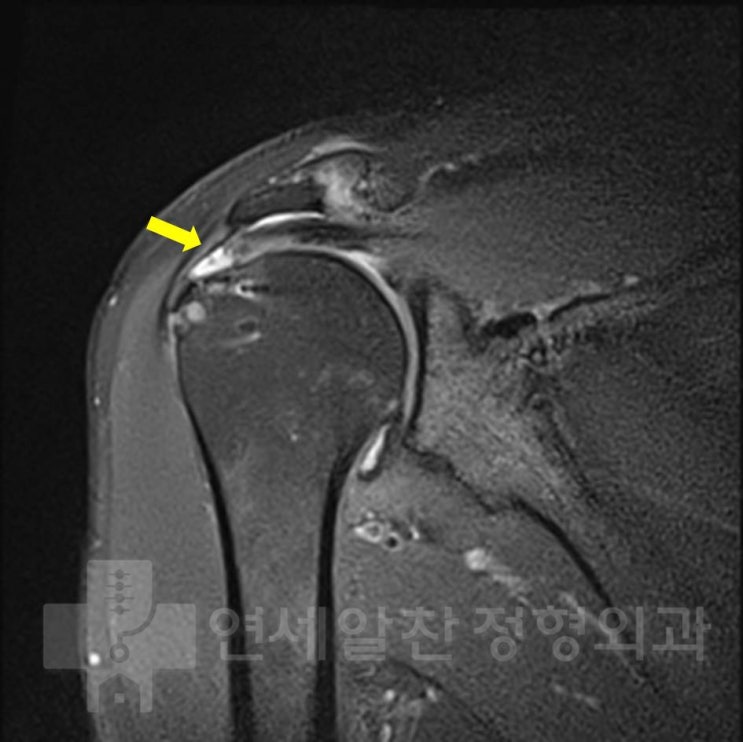

Revision Supraspinatus Repair After Re-tear Following Previous Rotator Cuff Surgery

#supraspinatus#re-tear#revision repair#rotator cuff#arthroscopy